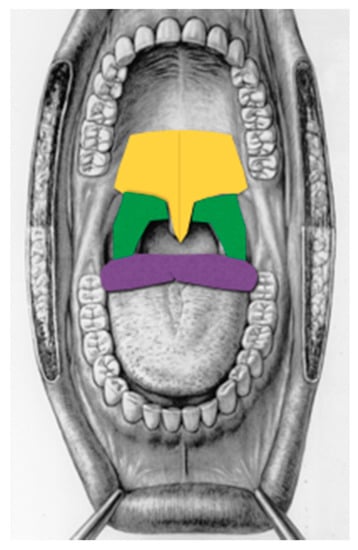

| Time of treatment | 30 min on the entire soft palate using the straight glass rod |

| 10 min of overlap on the so-called “main target point” using the straight glass rod. The main target point is the region of the soft palate midline posterior to the hard palate for an area of about 3 × 3 cm where the vibration of the soft palate begins (Figure 2) and, in the same region another three minutes of laser irradiation at 20 watts, frequency of 20,000 Hz, and 10 microseconds pulse duration (mean output of 4 watts) | |

| 10 min on lateral pharyngeal walls using either the straight or curved glass rod if needed (based on FNMM, which was compulsory before treatments in order to evaluate the exact region where the obstruction occurs) | |

| 15 min on the base of the tongue midline as far as possible holding the tongue with gauze (using the curved glass rod) if the FNMM showed an obstruction at that site. | |